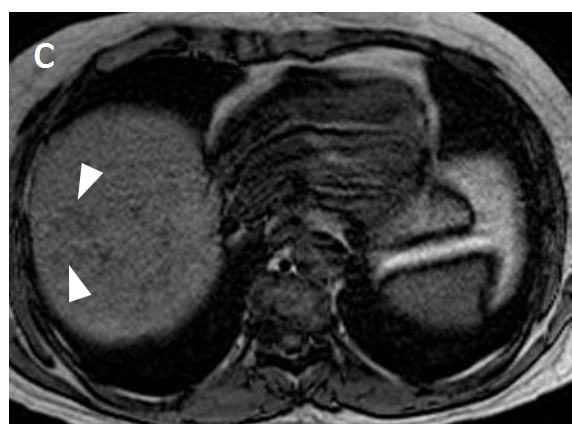

The presence of a capsule (Figure 12) is a major finding according to LI-RADS, but not EASL. The capsule is a characteristic feature of progressed HCC and is absent in dysplastic nodules or early HCCs. It shows low T1 and T2 signal intensity and enhancements on the portal and delayed phase at 3 min after contrast injection (or transitional phase if hepatospecific contrast agent is used); on the contrary, corona enhancement occurs earlier on the arterial phase. A capsule should be thicker than the fibrous septa of cirrhosis, which also show delayed enhancement. An intact capsule on imaging has been associated with lower recurrence rates after treatment [137], while extracapsular tumor extension predicts poor survival [138]. It should be stressed, however, that an encapsulated progressed HCC has a worse prognosis than an unencapsulated early HCC; the presence of a capsule confers a better prognosis only when the encapsulated tumor is compared to HCCs of a similar size and grade with breached capsules or without a capsule.

Figure 12. A large HCC is depicted in the right liver lobe of this 81-year-old man. The tumor is surrounded by a capsule, nicely seen as a thin, low signal line on the fat-suppressed T2 sequence (arrowheads) (a) and shows inhomogeneous but predominantly high T2 signal intensity. Areas of fat are clearly shown in the in/out of phase images (asterisk) (b,c). This marked heterogeneity is known as the “mosaic” pattern. After contrast administration, mottled arterial enhancement is noted (d); definite wash-out and capsular enhancement (arrows) are seen on the portal phase (e).

Fatty change is encountered in approximately 40% of early HCCs [143]. With increasing tumor size and histologic grade, fat usually regresses and the percentage drops to 6% in moderately-differentiated HCCs [144], only to increase again in highly de-differentiated tumors. This occurs along with the diminished arterial supply, suggesting a connection between reduced blood flow, hypoxia, and steatogenesis [145]. MRI is superior to CT in detecting fatty change with the use of chemical shift sequences, which show the characteristic signal drop on the opposed-phase compared to the in-phase (Figures 12 and 13). Intratumoral fat can also be used to exclude cholangiocarcinoma, which is also associated with cirrhosis. Nevertheless, the added value of fat identification in a HCC is debatable because, when detected, other more suggestive features (like the vascular pattern) are already present [123].

When a smaller nodule is seen within a larger nodule, it implies de-differentiation of a cell subpopulation and progression towards hepatocarcinogenesis. The “nodule-in-nodule” sign suggests development of HCC within a dysplastic nodule (Figure 13) and the typical HCC features, such as the wash-in/wash-out pattern or diffusion restriction, are seen in the inner nodule. When numerous foci with different imaging characteristics are seen within a nodule, the appearance is known as a “mosaic” pattern and is usually encountered in large tumors (Figure 12), thereby facilitating the differentiation from cholangiocarcinoma [54].